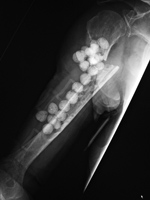

Antibiotic beads

The antibiotic laden cement beads were placed in an area of infected bone after removal of a infected fixation plate.